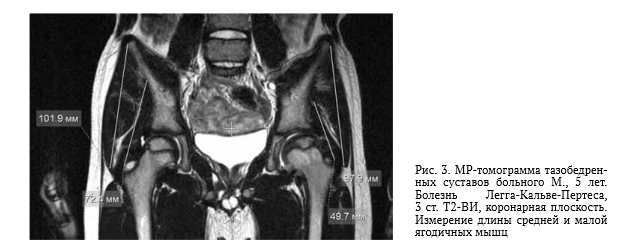

Болезнь пертеса причины

Болезнь пертеса причины 110 фото